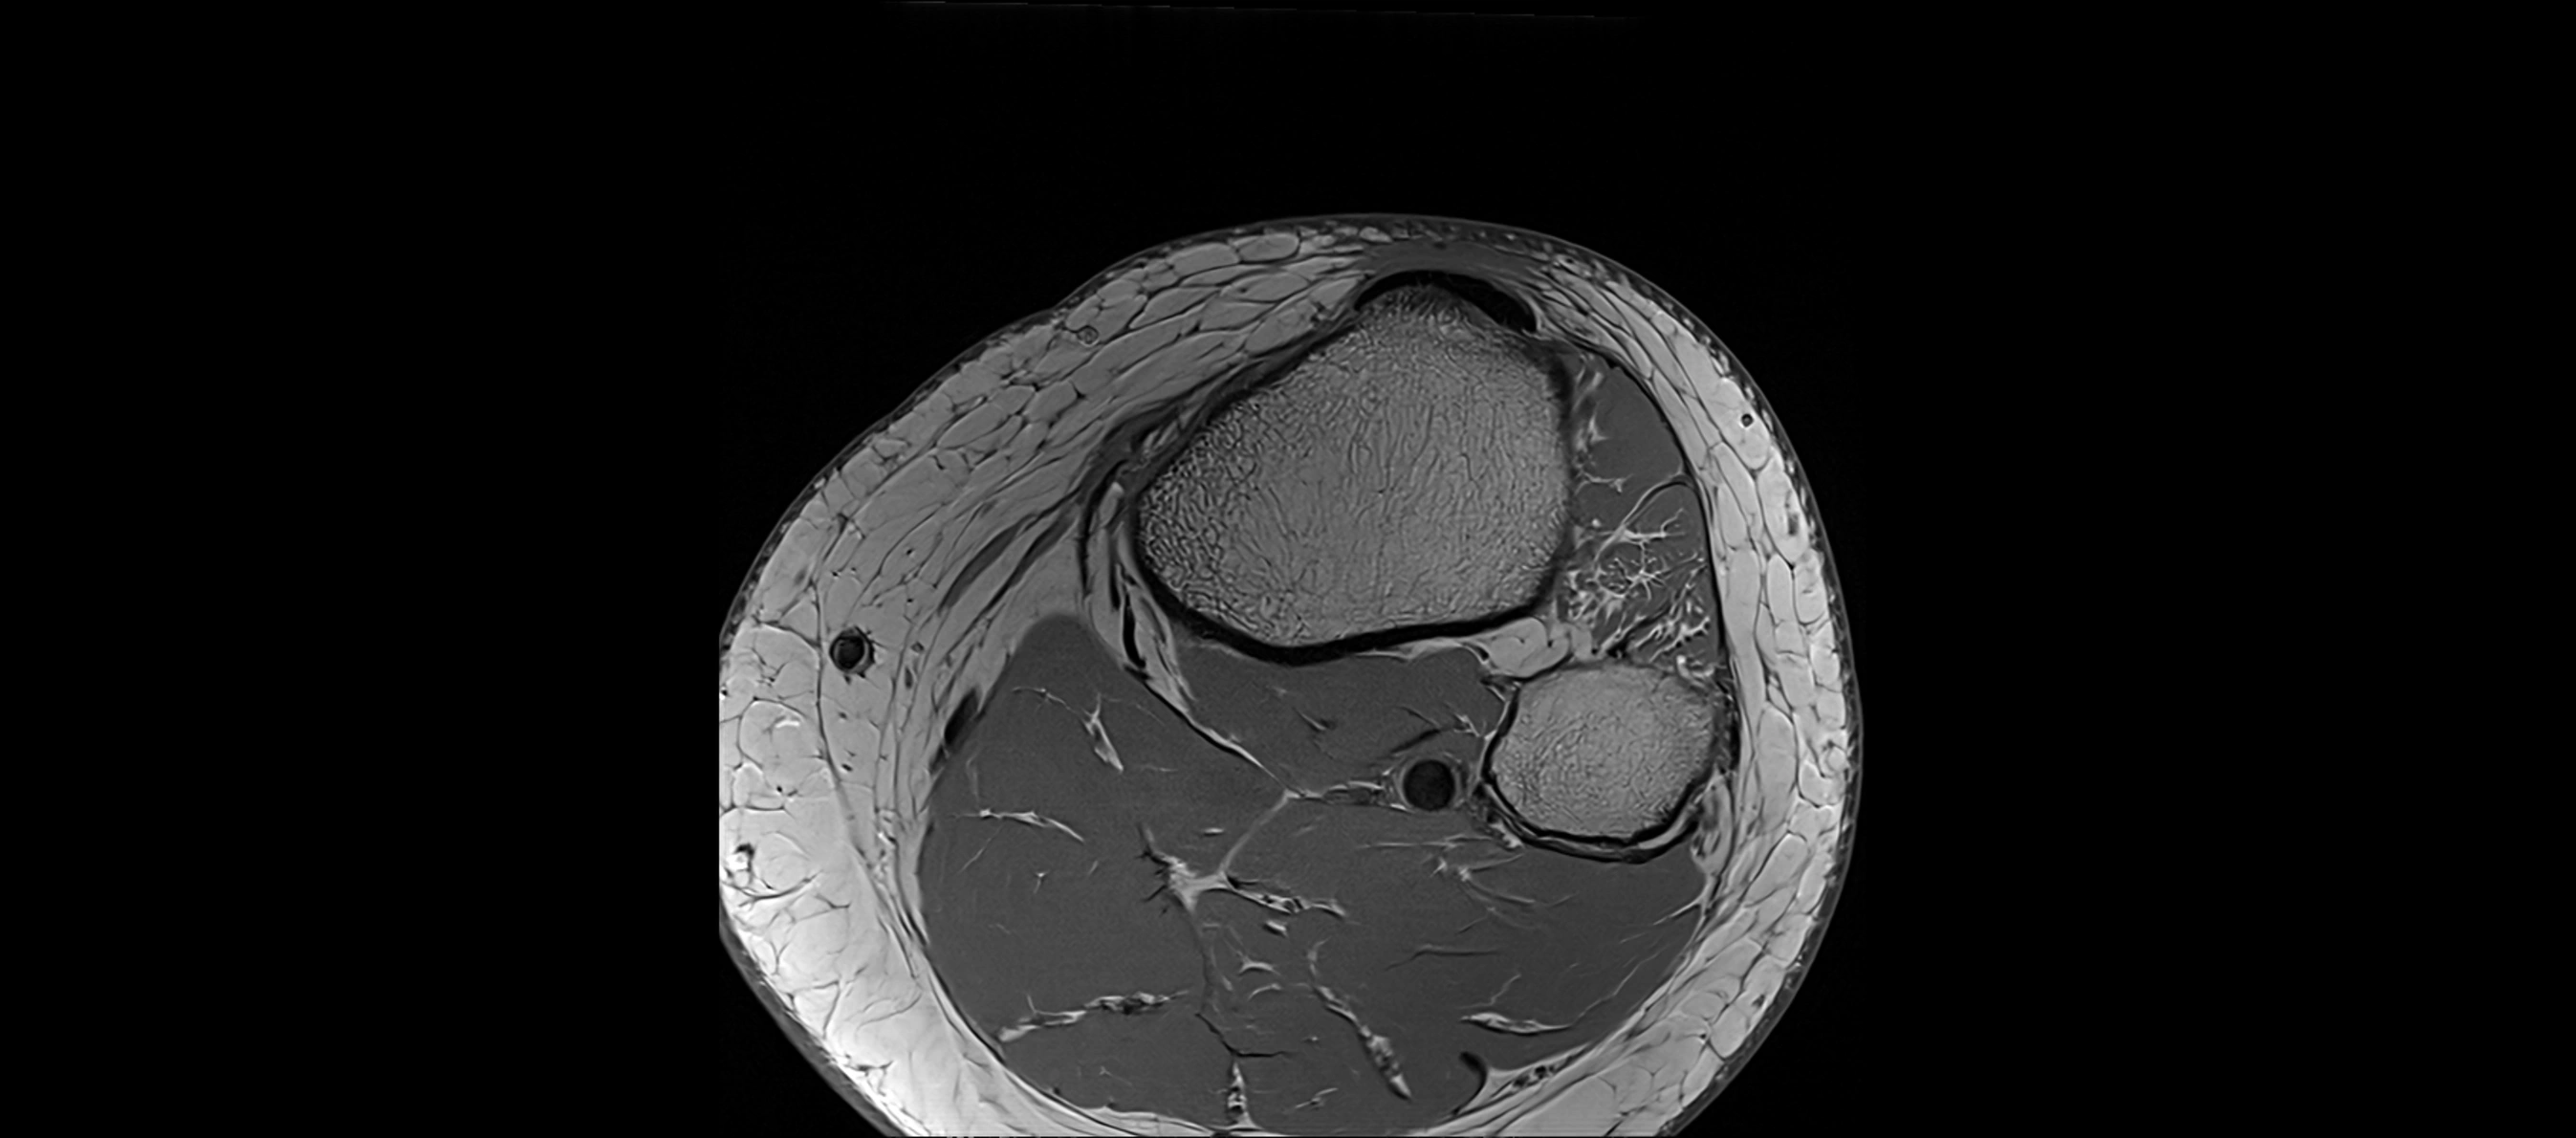

MRI Appearance

T1-weighted images:

• Normal ACL appears as a low-signal band-like structure crossing the intercondylar notch

• Surrounded by intermediate signal synovial fluid and fat planes

T2-weighted images:

• Normal ACL remains low signal

• Partial or complete tears appear as discontinuity, increased signal, or fiber laxity

MRI images

image